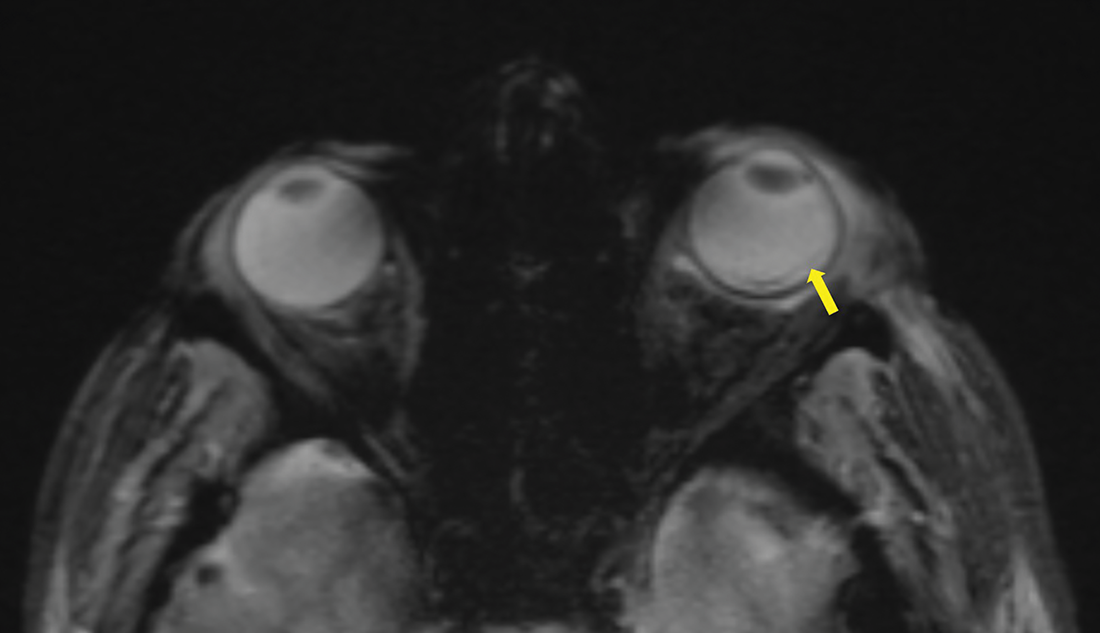

After ruling out cavernous sinus thrombosis with a contrast‑enhanced CT scan, a brain MRI was performed, confirming the diagnosis of endophthalmitis. MRI showed pre‑septal orbital cellulitis, with pre‑septal enhancement seen on the 3D T1 Dixon sequence (Figure 1, arrowhead). This was associated with increased scleral enhancement and alterations at the junction between the left ocular globe and the optic nerve (Figure 1, arrow). Of note also the slight increase in T1 signal of the vitreous body (Figure 1, star). There was choroidal and peri‑septal inflammation with fat saturation after contrast injection, and in the 3D FLAIR sequence, showing a pre‑septal and peri‑optic hypersignal (Figure 2, arrowheads). Additionally, there was an increased signal in the choroid and ciliary body, as well as thickened dura mater, in relation to the meningitis (Figure 2). Axial T2 gradient echo sequences showed retinal detachment and inflammation around the distal portion of the optic nerve, with a slight linear hypoT2 signal (Figure 3, arrow).

Figure 3

Axial T2 gradient echo sequence showing a retinal detachment with a slight linear hypoT2 signal (arrow).